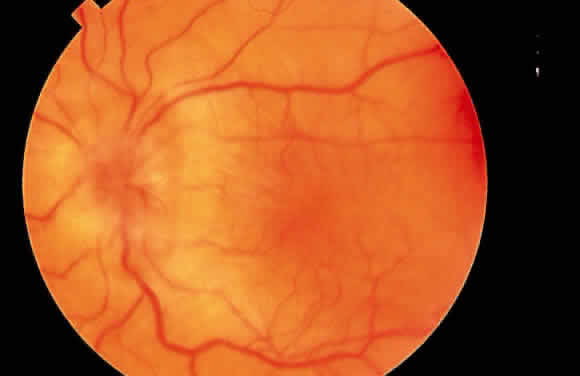

Hypotony Maculopathy

Some patients with intraocular hypotony develop loss of central vision secondary to marked irregular folding of the choroid and retina. Initially, these folds are broad and not sharply delineated. They tend to radiate outward in a branching fashion temporally from the optic disc and concentrically or irregularly nasally to the disc. There may be swelling of the peripapillary choroid simulating papilledema (Fig. 3). The retina often shows a series of stellate folds around the center of the fovea. The retinal vessels are tortuous and sometimes engorged. The primary cause of visual loss is the marked folding of the central retina. Early detection of this condition is important because correction of the cause usually results in visual improvement. In cases of prolonged hypotony, permanent pigmented lines, caused by changes in the retinal pigment epithelium, occur in the macular area and nasally. A postoperative bleb leak and a cyclodialysis cleft were formerly the most common causes of hypotony maculopathy. The incidence of hypotony maculopathy after glaucoma surgery has increased with the use of antifibrotic agents, specifically mitomycin C. A direct toxic of mitomycin cannot be ruled out. The maculopathy is most likely to occur in young myopic patients, who may have a sclera more susceptible to swelling and contraction.11–14